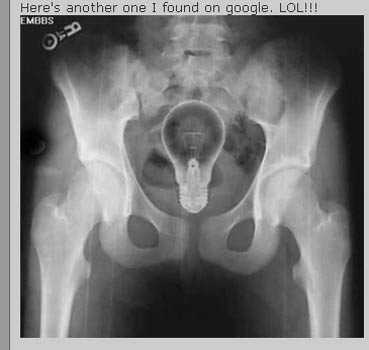

Trong trường hợp này thì sáng kiến nhét bóng đèn vào người lại là một tối kiến.

Attached Thumbnails

Click image for larger version

Name:	images1025035_ct4.jpg

Views:	9

Size:	18.7 KB

ID:	416978